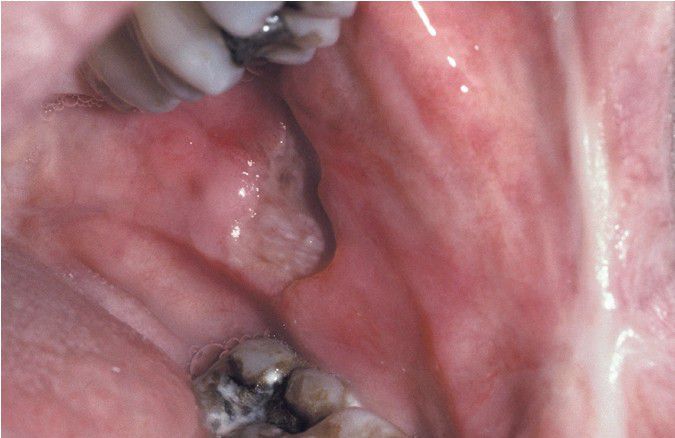

Major Aphthous Ulceration.

Large, deep, and irregular ulceration of the posterior buccal mucosa. Note extensive scarring of the anterior buccal mucosa from previous ulcerations